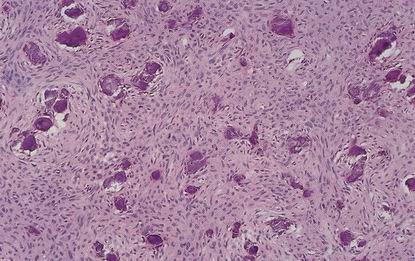

Mesenchymální - maligní

Fibrosarkom

Maligní fibrózní histiocytom (MFH)

Angiosarkom + Kaposiho sarkom

Liposarkom

Osteosarkom

Chondrosarkom

Leiomyosarkom

Rhabdomyosarkom

Synoviální sarkom